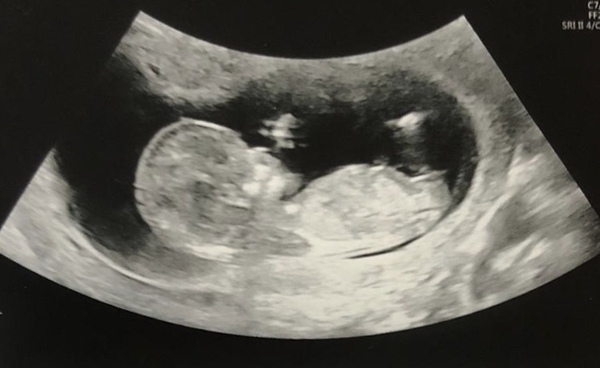

😊 one chilled little baby just hanging out! Was very well behaved and easy to measure. After being a couple of days behind it’s now measuring a couple of days ahead but they’ve left my EDD the same as we know exactly when it was conceived! Feeling much happier and more reassured now and we have finally told our family and a few friends 😊

That's a wonderful clear photo @DobbieFreeElf! Congratulations!

@DobbieFreeElf what a lovely picture! Glad the scan went well!

Amazing, congratulations @DobbieFreeElf that's great news, fabulous scan pic and a relief after the bleeding I'm sure. Hope you can relax and enjoy now (not that I'm entirely practicing that 🙈) Is there anyone else to have a 12 week scan or is that the full house?

@DobbieFreeElf congratulations! That is a lovely clear scan! It looks like s/he is sucking it's thumb!

Thanks everyone! Yes @FlapJackered either thumb sucking (or smoking according to my sister 🤣)